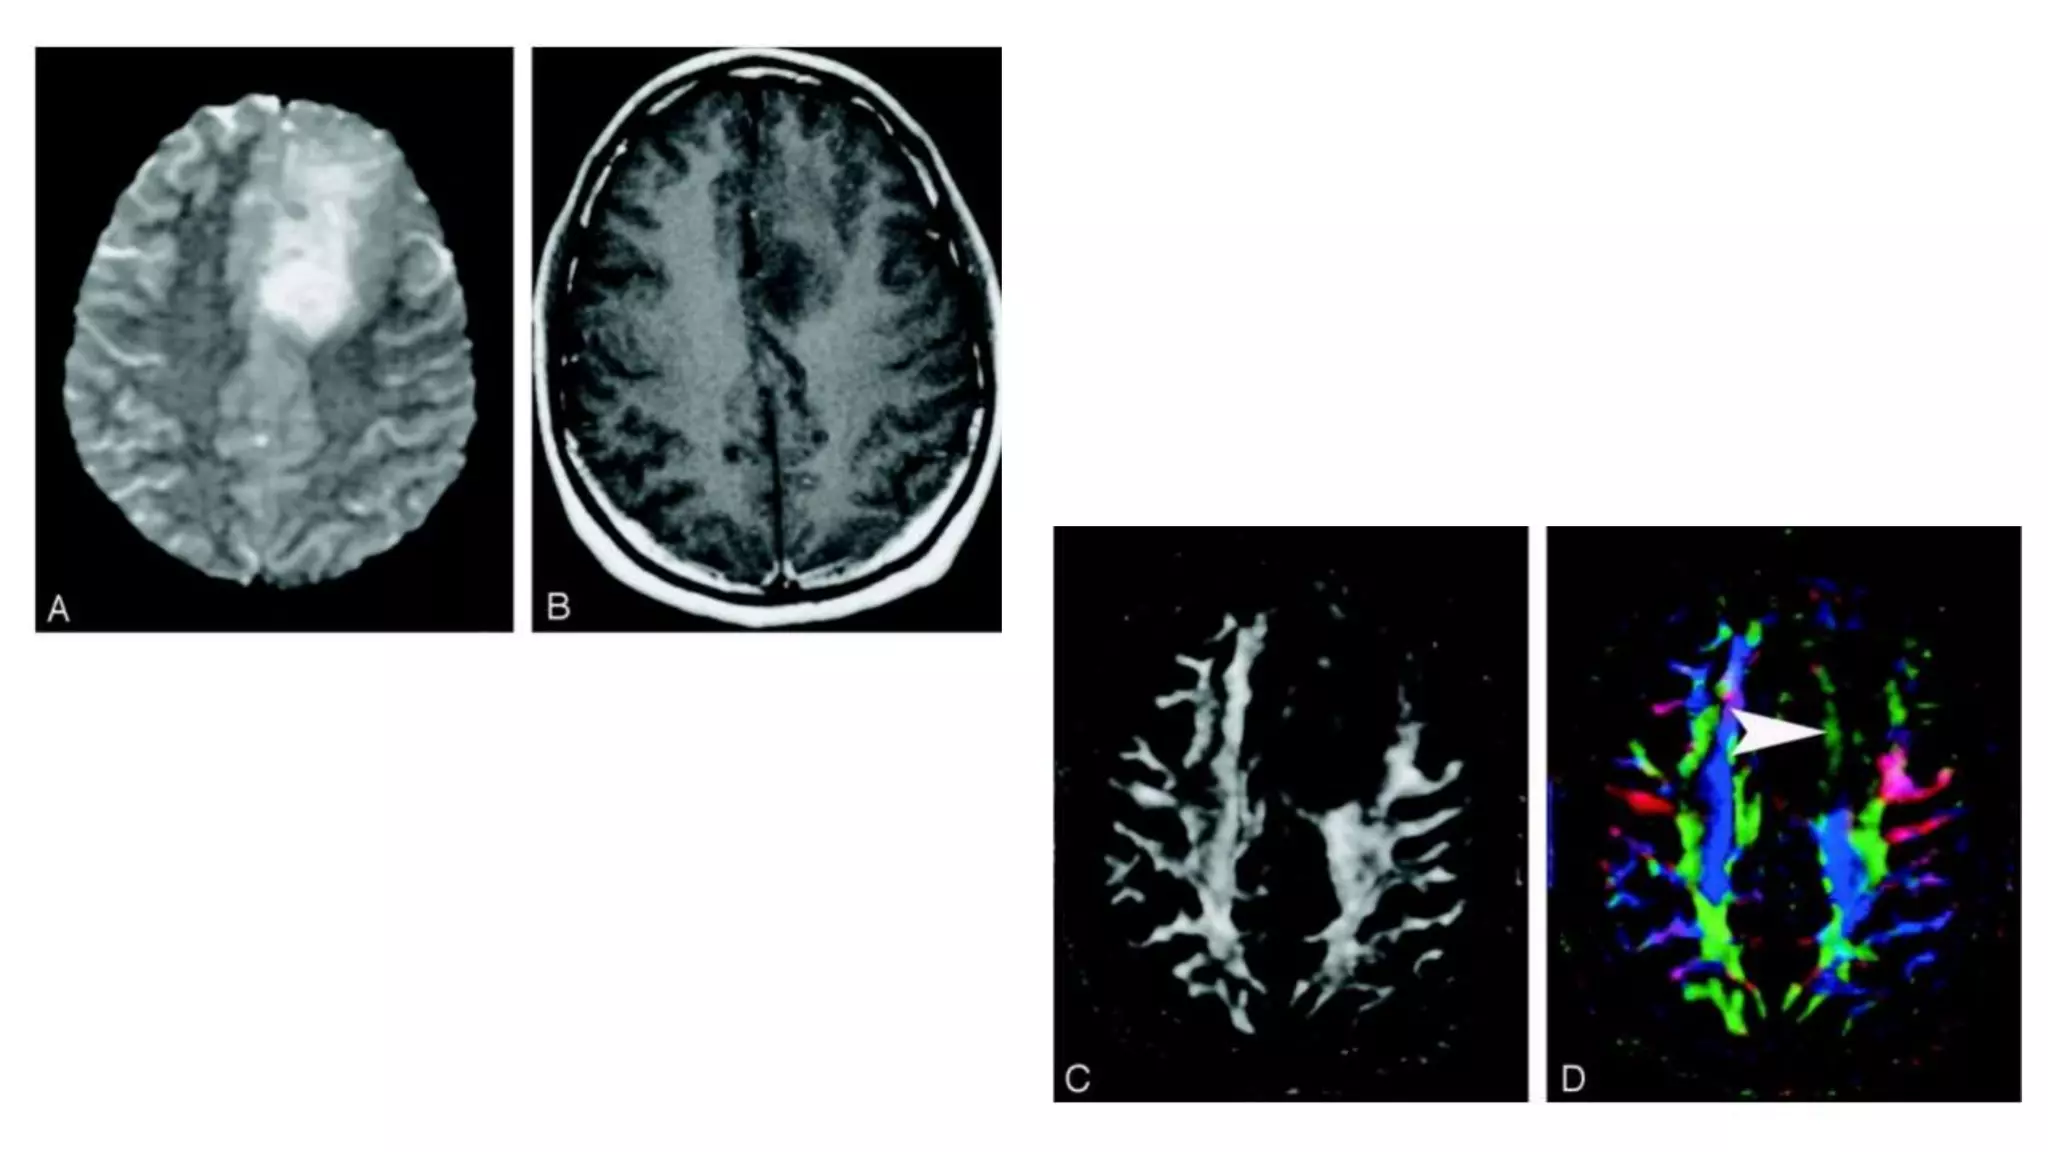

• #61 DTI pattern 3: abnormal (low) anisotropy, abnormal orientation. This infiltrating astrocytoma is characterized by both diminished anisotropy and abnormal color (arrowhead) on the directional map, suggesting disruption of WM fiber tract organization more severe and complex than that seen with pattern 2 . Note that the color change cannot easily be attributed to bulk mass effect as in purely deviated tracts.

• #62 DTI pattern 4: near-zero anisotropy, tract unidentifiable. This high-grade astrocytoma has destroyed the body of the corpus callosum, rendering the diffusion essentially isotropic and preventing identification on the directional map (arrow). This pattern can be useful in preoperative planning that no special care need be taken during resection to preserve a tract.